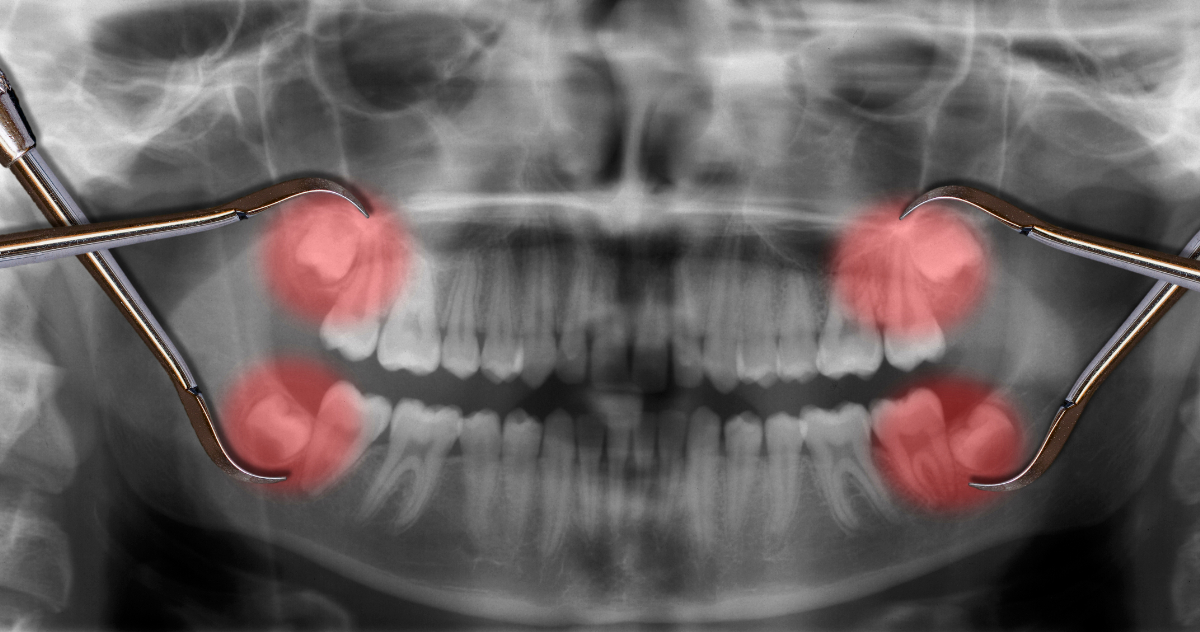

親知らずとは、正式には第三大臼歯(だいさんだいきゅうし)と呼ばれる、10代後半から20代にかけて生え始めることが多い歯です。現代人は顎が小さいことが多く、すべての親知らずが問題なく生えるとは限りません。親知らずが横向きや斜めに生えたり、一部だけが歯ぐきから出たりする半埋伏歯(まいふくし)になる例も多く見られます。

智歯周囲炎とは、親知らずの周囲に炎症が起こる状態で、一般的なトラブルのひとつです。多くの場合、親知らずが半分埋まったままの状態(半埋伏)で生えていて、歯と歯ぐきの間にできた隙間に細菌が侵入することで発症します。